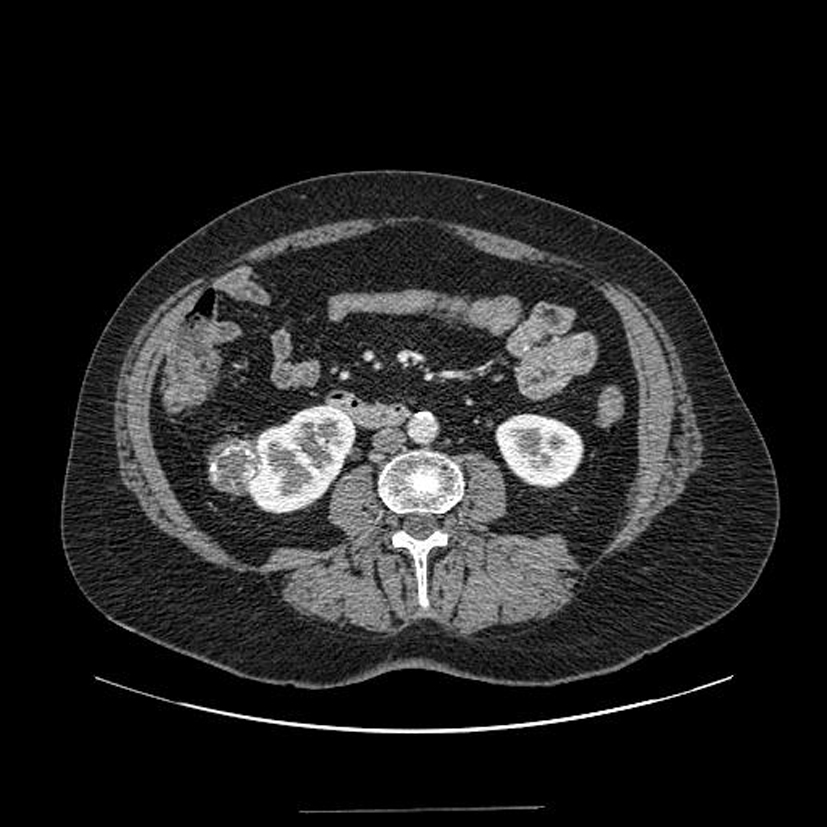

Diagnostic?

Petite tumeur rénale droite trouvée de manière fortuite sur un scanner